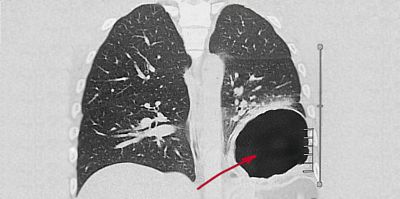

Пациенту, в экстренном порядке выполнена компьютерная томография грудной и брюшной полостей, при которой выявлена дислокация 2/3 желудка в левую плевральную полость (диафрагмальная грыжа).

«В связи с клинико-диагностическими признаками ущемления диафрагмальной грыжи, пациент в экстренном порядке взят в операционную, где при диагностической лапароскопии выявлен травматический разрыв левого купола диафрагмы со смещением в левую плевральную полость большей части желудка, сальника, левой доли печени», - рассказывает заведующий отделением экстренной хирургии Московской областной больницы имени профессора Розанова В.Н. Артем Александрович Косов.